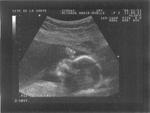

sem 20 écho-2 bébé Catherine

Date : 25/11/2006 Affichages : 731